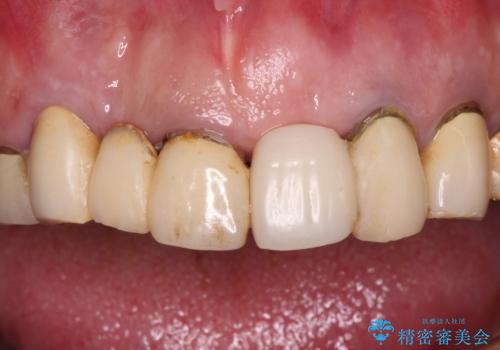

転倒で折れてしまった前歯 インプラントによるオールセラミックブリッジ治療

- 転倒により前歯3本が折れてしまったとのことで、インプラントによる治療を希望して来院された患者様です。

既に近医で真ん中の歯1本は抜歯されており、その隣の2本も破折していると言われたとのことでした。

診断をした結果、前医の診断の通り、2本とも破折しており、既に抜去している歯を含めて3本の抜歯が必要な状態でした。

抜歯する歯の両隣も治療が必要と思える歯であったため、広範囲なオールセラミックブリッジによる治療も提案しましたが、患者様本人の希望もあってインプラント2本による欠損部のみのブリッジ治療を行うこととしました。

治療により前歯は非常に安定しましたが、インプラント部の両隣、特に反対側の前歯はクラウンのやり直しが必要な状態であったので、今後反対側の治療も実施していく予定です。